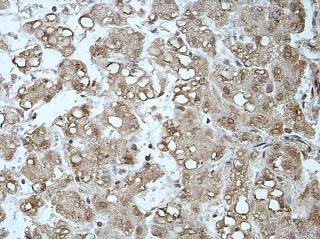

Mast cell-like coagulase [Mast Cell Chymase (MCC)] is an important marker of mast cells, one of the major proteases secreted by mast cells, and an important mediator of inflammation. It is used to study the distribution of mast cells in the skin, synovium, lungs, and heart, as well as research on the diagnosis and treatment of related diseases in which mast cells are involved.

MCC antibody reagents can specifically bind to MCC antigens. Immunohistochemical kits containing MCC antibody reagents are suitable for assisting in the assessment of hereditary tumor risks due to MCC gene mutations or abnormal protein expression.